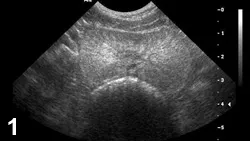

FIGURE 2

CBPH sagittal view (ventral is top of image, cranial is left) of a canine prostate with small anechoic parenchymal cysts.

• Characteristic appearance of BPH and CBPH on ultrasonography includes symmetric parenchymal striation with increased echogenicity and variable hypoechoic-to-anechoic intraparenchymal cystic structures (Figures 1 and 2).